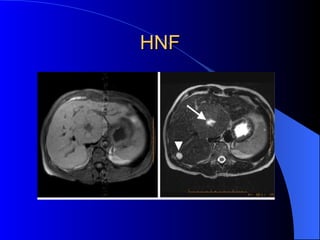

Hiperplasia nodular focal Mas frecuente en mujeres en edad fértil. Anticonceptivos Asintomaticos Cicatriz central 30%

HNF